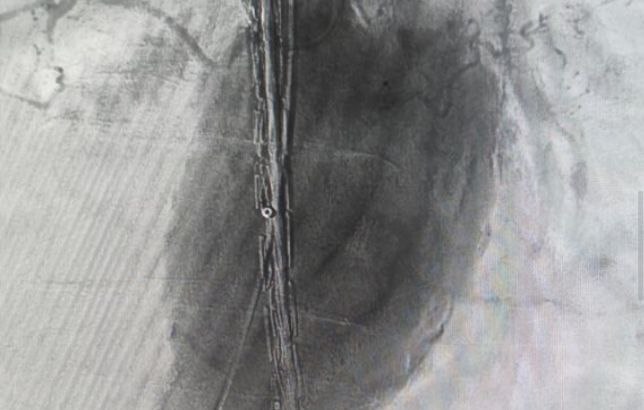

По множеству противопоказаний открытое вмешательство подвергло бы жизнь пациента высокому риску. Специалисты приняли решение о применении эндоваскулярного метода для установки стент-графта.

«Стент-графт – комбинация стента (металлической или полимерной сетки, которая поддерживает стенку сосуда) и графта (тканевой или синтетической оболочки), который обеспечивает дополнительную прочность и защиту. Конструкция укрепляет стенку аорты изнутри, создавая новый прочный канал для кровотока», – объяснили в облздраве.

Таким образом удалось восстановить функцию магистрального сосуда.